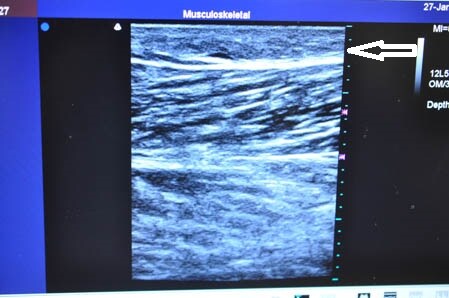

画像上しっかりと皮下脂肪は根こそがれており

間違いなく患者様のご期待にはそえられると思います。